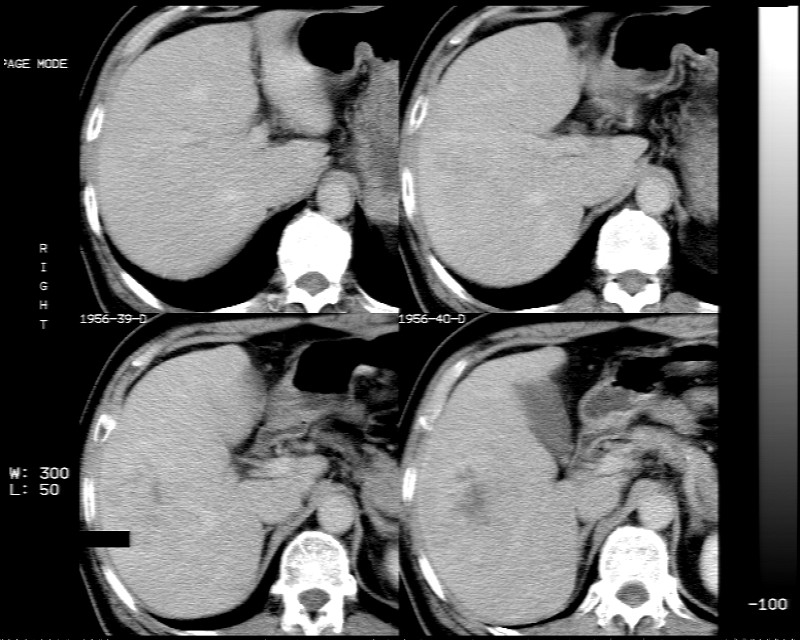

男 73岁 b超检肝右叶占位病变,afp阴性. 随访中.

肝脏右叶块状低密度影,增强后动脉期明显强化,门脉期强化减低,延迟期病灶又成低密度。考虑肝细胞癌。我认为比较典型。

低密度肿块,动脉期明显强化,可见星状低强化区,门脉期强化向中心扩展,但病灶动脉期强化最明显,门脉期及平延迟期强化减低,结合病只考虑巨大局灶性结节增生,血管瘤不除外

肝右叶块状低密度影,增强后动脉期病灶明显强化,门脉期及延迟期强化减低。

考虑血管瘤可能性大。

肝右叶巨大占位性病变,平扫呈低密度改变,增强扫描动脉期病灶周围强化,门脉期强化未退出,延时期病灶周边强化与肝实质接近,病灶中心在各期均可见星状不强化区;首先考虑局灶性结节增生可能性大,其次为血管瘤。肝癌不能完全排外(不首先考虑肝癌是因为强化不支持快进快出特点)。

平扫示:肝右后叶下段内见类圆形略低密度占位病灶,边界尚清楚,最大径约为102×71mm,ct值31~41hu。

动态增强扫描示:动脉期病灶显著不均性强化,病灶强化密度高于肝实质;平衡期病灶呈等密度;延迟扫描病灶密度略低于肝实质;三期均见占位病灶内有裂隙状无强化影。肝内胆管无扩张,腹膜后未见肿大淋巴结。

拟诊:肝右后叶下段内占位性病变,考虑为肝结节样增生。

建议进一步检查(mri/或穿刺活检),不排外肝ca。